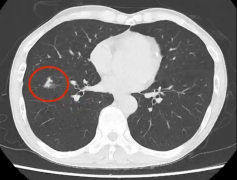

胸部CT常见的影像表现及对应的诊断要点环医疗1

- 环医疗胸部CT常见的影像表现及对应的诊断要点